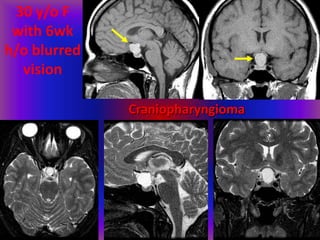

30 y/o F

with 6wk

h/o blurred

vision

Craniopharyngioma